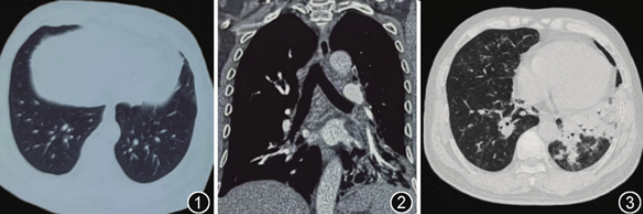

术后患者指氧饱和度为90%(鼻导管吸氧4 L/min),阵发性剧咳和憋气,无声音嘶哑,2024年2月17日行支气管镜检查,镜下见喉部黏膜充血,未见坏死,声门开合良好。气管支气管黏膜弥漫覆盖黄色脓性假膜,部分黏膜糜烂坏死;右肺下叶背段开口明显狭窄,黏膜粗糙,无糜烂坏死,行支气管黏膜活检;左肺下叶黏膜严重坏死,见多发溃疡,行支气管肺泡灌洗,灌洗液为黄色,量50 ml(图4)。肺泡灌洗液mNGS仅检测出金葡菌,序列数为6 300(lukF-PV 序列数4)。肺泡灌洗液涂片查见革兰阳性球菌,细菌+真菌培养阴性,抗酸染色阴性,肺泡灌洗液GM试验<0.1 S/CO。支气管黏膜病理示重度急性炎症(图5)。改用利奈唑胺(600 mg,1次/12 h,静脉滴注)抗感染治疗,治疗5 d后,指氧饱和度为94%(未吸氧),复查胸部CT平扫示双肺多发斑片状阴影吸收(图6),第6 d复查支气管镜见气道内黏膜较前好转,可见较多分泌物并给予吸引(图7),第9天复查支气管镜,气道内黏膜较前进一步好转(图8)。

图4 利奈唑胺治疗前支气管镜检查镜下表现,图4A为主气道,气道内弥漫覆盖黄色脓性假膜;图4B为左下叶支气管黏膜糜烂坏死

图5 利奈唑胺治疗前气管镜下右肺下叶背段黏膜活检,病理见重度急性炎症,黏膜腺体间见大量淋巴细胞、中性粒细胞浸润,伴新生小血管形成 HE 低倍放大

图6 2024年2月23日利奈唑胺治疗5 d后复查胸部CT平扫示双肺下叶多发斑片影基本吸收

图7 利奈唑胺治疗6 d复查气管镜,气道内黏膜好转

图8 利奈唑胺治疗9 d复查气管镜,气道内黏膜进一步好转